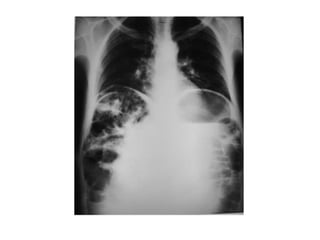

• Íleo paralítico

– Dilatación de intestino grueso, delgado e

incluso estómago

– Puede haber dilatación segmentaria (asa

centinela) en intestino cercano a zona

inflamatoria

– Escasos niveles hidroaéreos